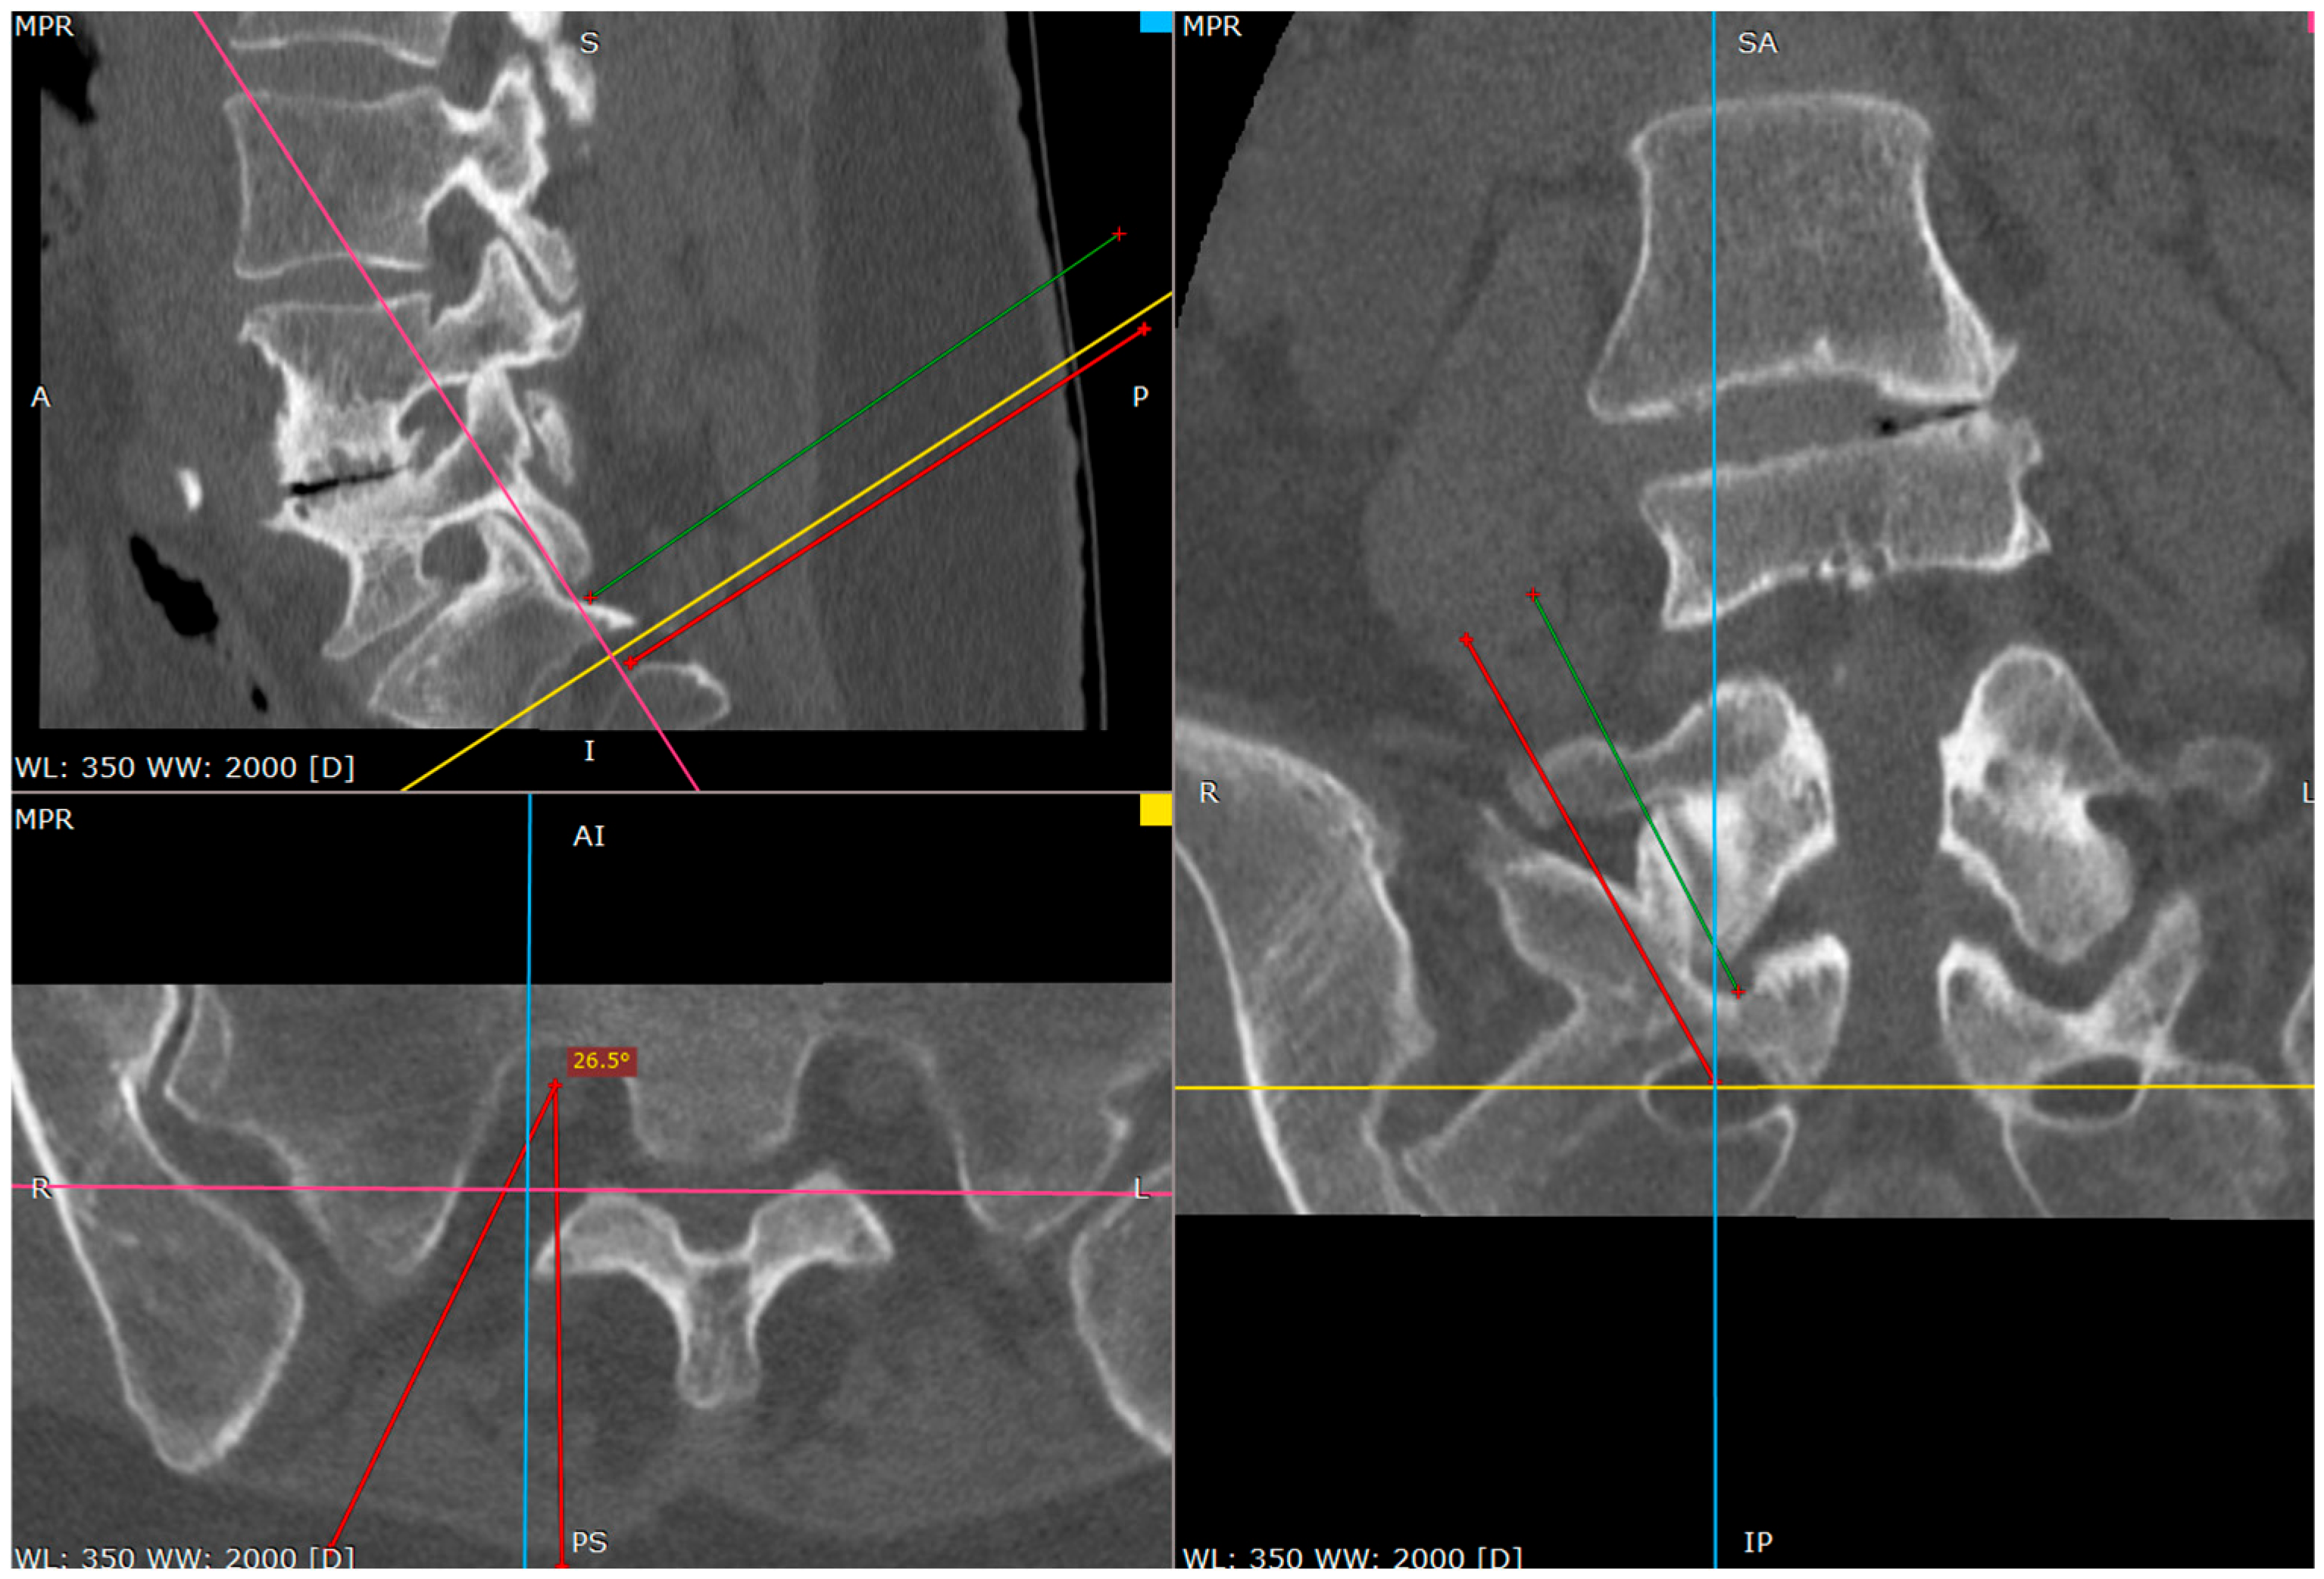

Figure 8. Approach angle and needle trajectory to facet with intent to approach S1 root (CT tri-plane reconstruction).

Jcm 14 03126 g008

Figure 9. Approach angle and needle trajectory to S1 root (CT tri-plane reconstruction).

At this phase we start to wander to the caudal direction with the tip of the needle by tapping, moving the tip with a gentle reversing–advancing movement, as well as the twisting of the bended tip (Figure 6).

In a short distance the needle loses the bony contact as it reaches the dorsal foramen of the S1/S2 segment.

It is beneficial to remember the level of it. If we do not perform it by then, the needle can be reversed and placed on the brink of the opening, to give an idea of what the depth is at the start of the opening.

From this point we can gently advance the needle 2–3 cm before we confirm the depth of the needle on the lateral view.

The proper placement of the tip can be confirmed with the contrast administration, fluoroscopy verification or clinical response with the S1 root distribution sensation after the tip of the needle contacts the S1 sheath. Therefore, at this part one should be cautious. We usually use the 1% lidocaine solution to produce the hydrostatic pressure cushion at the tip of the needle, while advancing the needle, as well as a larger needle that poses less risk of penetrating the root sheath. Also, the tapping activity over the bone blunts the tip of the needle, decreasing the risk of root injury (Figure 7, Figure 8 and Figure 9).